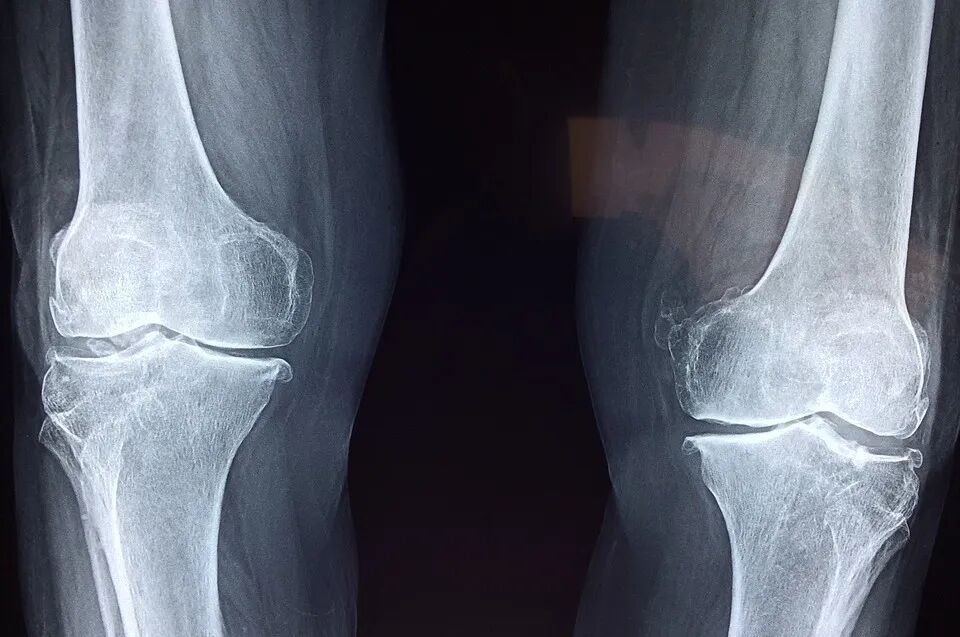

类风湿关节炎:原来是细菌惹的祸?

类风湿关节炎(RA)是一种病因未明的慢性、以炎性滑膜炎为主的系统性疾病。类风湿关节炎高风险人群在出现明显临床症状前常会被检测到高水平自身抗体(即类风湿因子,RF)的存在,如IgG-RF及IgA-RF。但这些抗体的起源一直是个谜。

最近,美国科罗拉多大学医学院风湿病科 Kristine A. Kuhn 团队发现,分离于RA高危人群的自身抗体IgA和IgG可与瘤胃球菌科(Ruminococcaceae)及毛螺菌科(Lachnospiraceae)肠道细菌发生交叉反应。进一步分析证实,一种Subdoligranulum属细菌与自身抗体的产生密切相关。将Subdoligranulum属细菌的特定分离株 “定植” 到小鼠肠道后,小鼠血液会出现自身抗体IgG,后者在关节沉积,导致小鼠产生与RA临床发病早期相似的关节肿大现象。该研究提示,特定肠道细菌可能在RA的发病过程中扮演着重要角色。